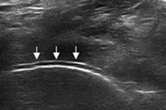

骨质侵蚀

跖趾关节骨质表面的不连续即为骨质侵蚀

软组织受损

肿胀关节内部回声不均匀,痛风结节周围软组织边缘欠规则。